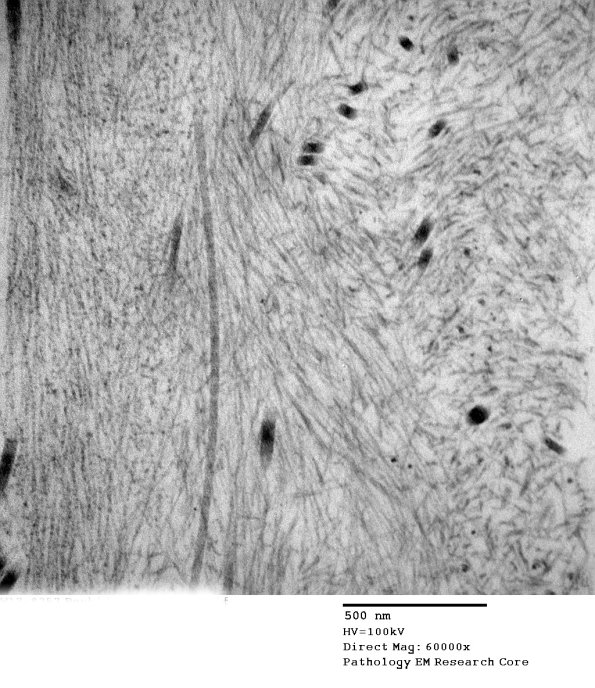

At low magnification the pale material might be mistaken for oxytalan; however, higher magnification identifies the material as filamentous amyloid. (electron micrographs)